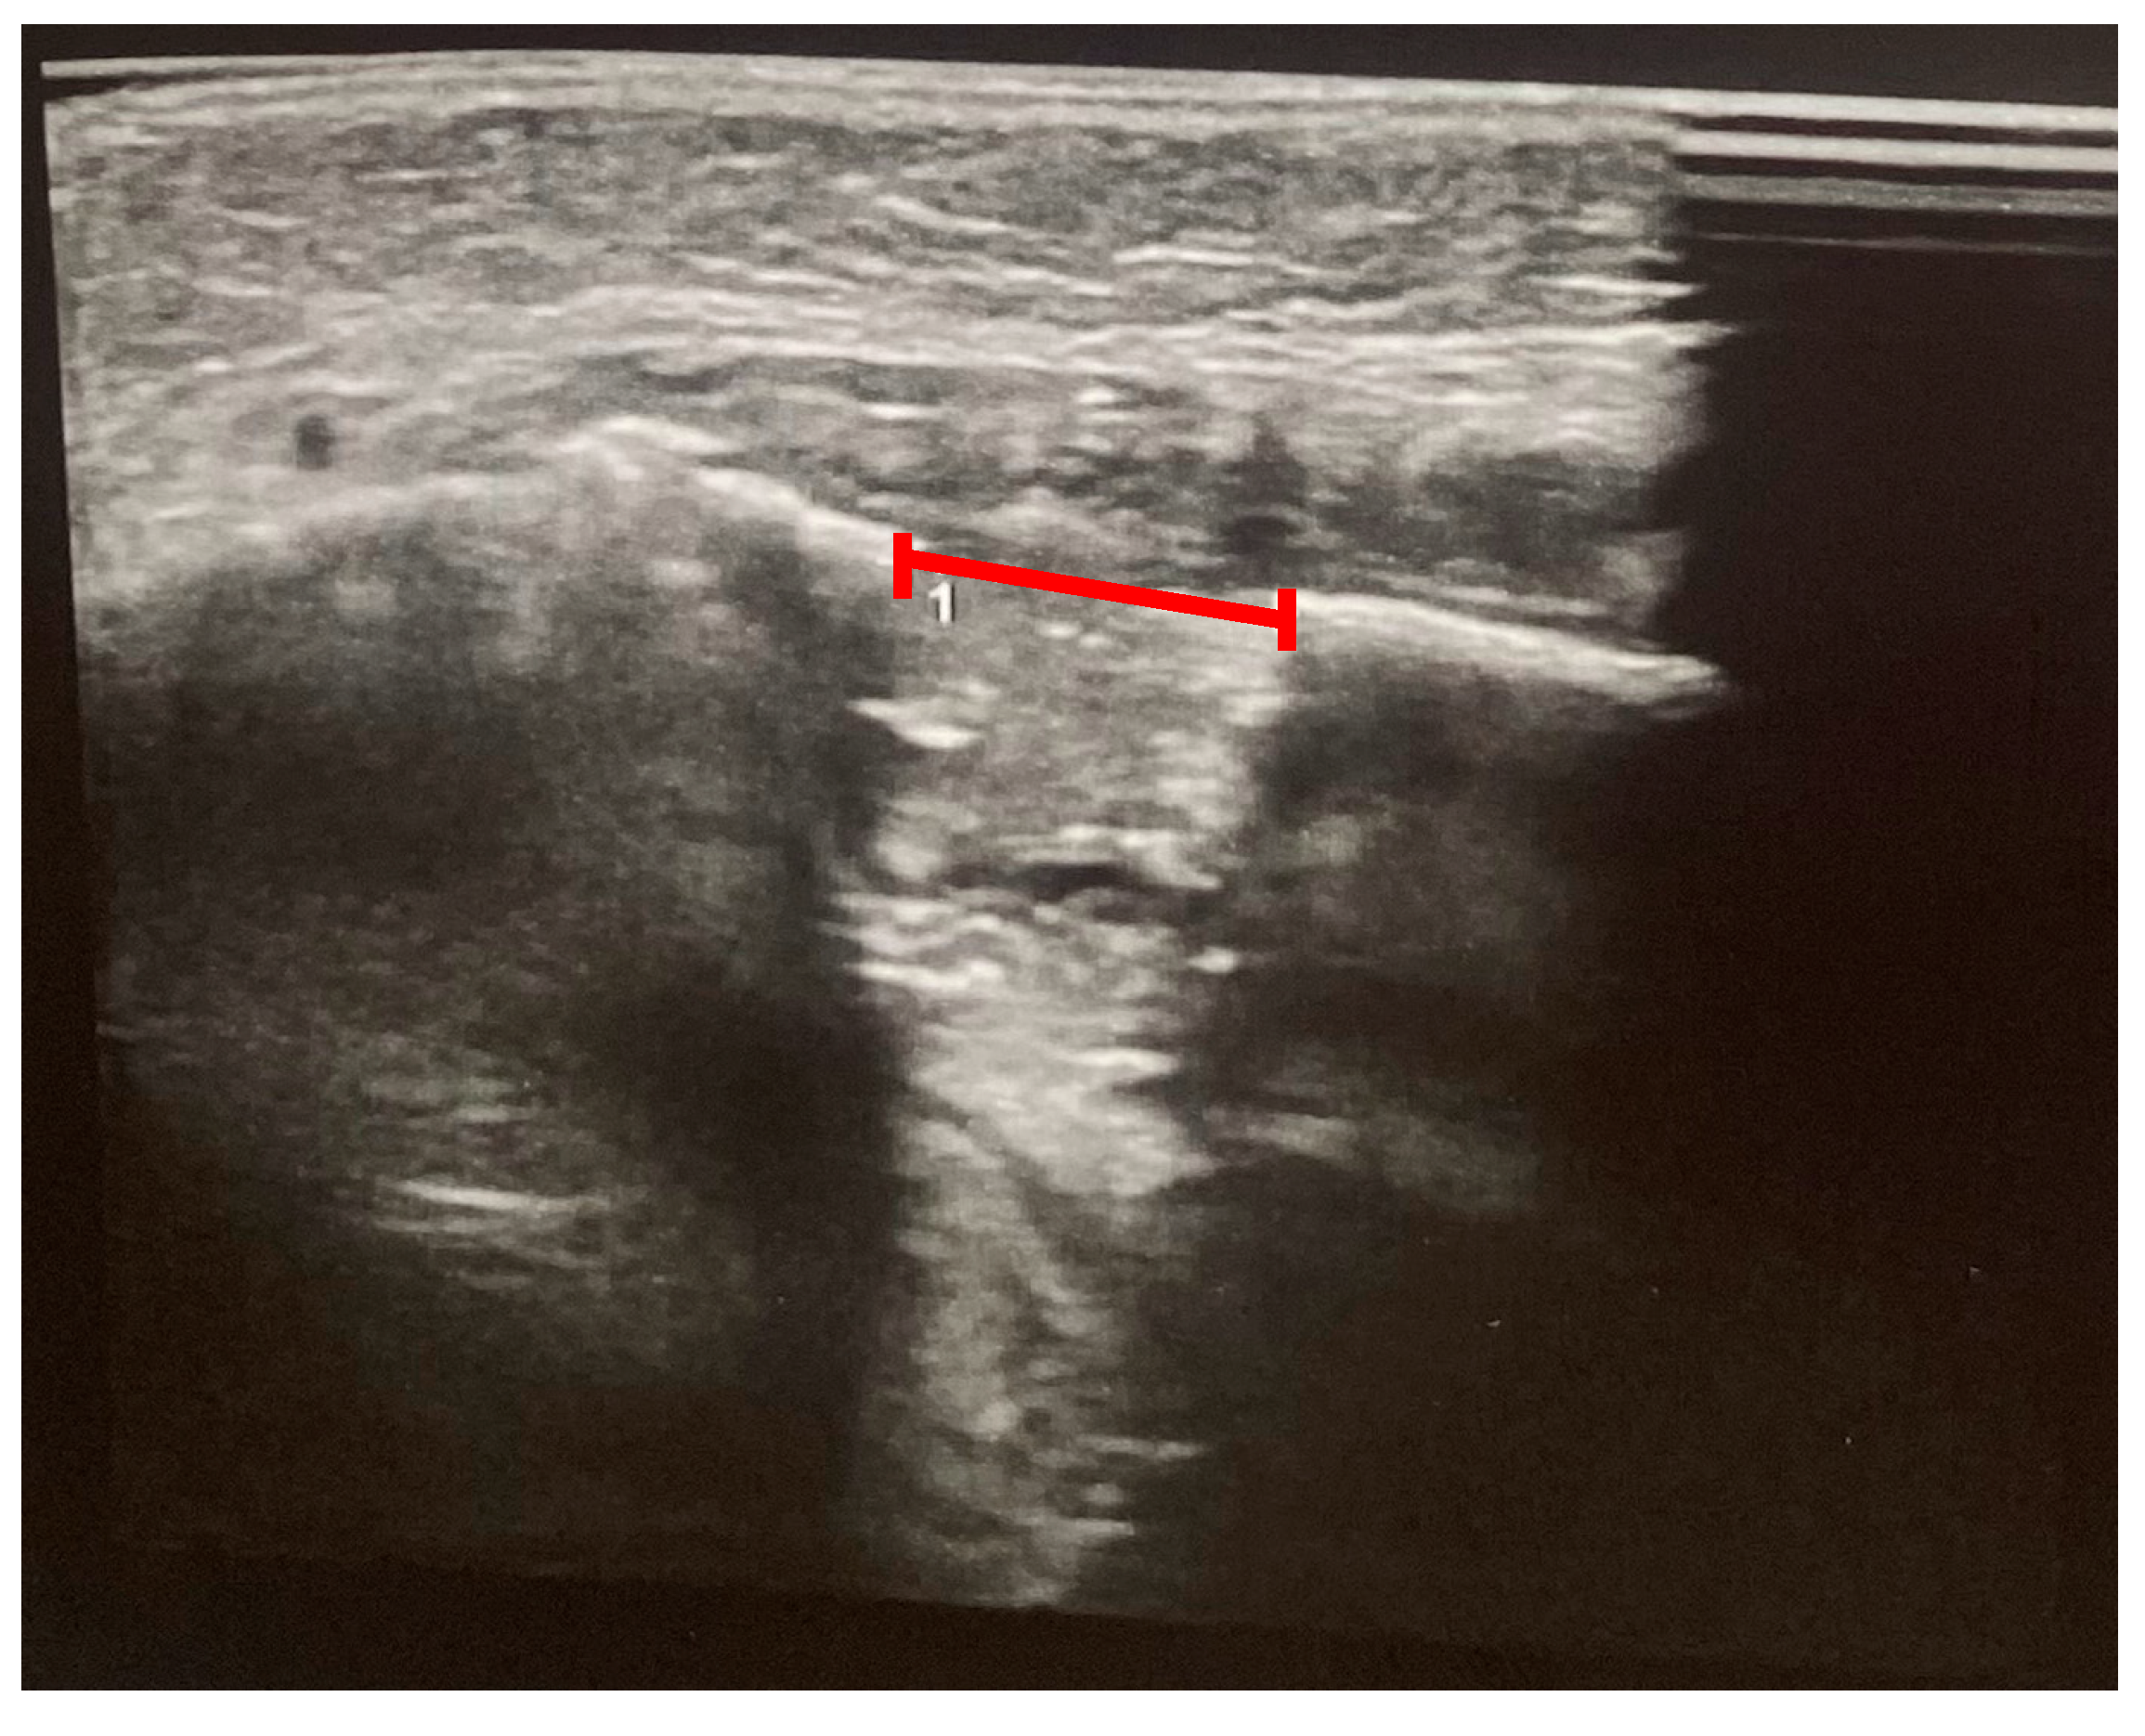

Ultrasound-based monitoring was initiated on the third day of the consolidation phase to evaluate the position and symmetry of the distractors and to assess early callus formation. Examinations were performed using the ARIETTA 750 ultrasound system (Fujifilm, Lexington, USA) equipped with a 13 MHz linear transducer, without sedation. The probe was placed on the lateral aspect of the mandibular body and angle and oriented perpendicular to the cortical surface. At each examination, both the cranial and caudal cortices adjacent to the osteotomy were scanned in longitudinal and transverse planes, with particular attention to the metal distractor body, the osteotomy gap, and surrounding soft tissues. The distraction gap was measured between the echogenic cortices at the osteotomy site, and color Doppler imaging was used to assess vascularity within the developing callus. Ultrasound was performed at days 6, 21, and 42 (week 6) after surgery and again at weeks 6 and 16 after completion of distraction, in parallel with clinical and radiographic follow-up.

During the distraction and consolidation phases, we recorded the condition of the callus and its subsequent ossification by combining panoramic images and ultrasound examinations. Ultrasound examinations were performed with a 13 MHz linear transducer, without sedation. The ultrasound beam was oriented perpendicularly to the bone surface. The distractors were identified by characteristic metal echoes, and the osteotomy gap was visualized clearly, given the contrast between the gap and normal bone. Initial ultrasound findings indicated early callus formation with visible ossification. The ossification gap was measured at both cranial and caudal margins, and Doppler imaging confirmed vascularity within the callus, with no signs of infection. Further ultrasound evaluations were conducted at 6 and 16 weeks post-distraction, assessing the same parameters. Callus ossification progressed without signs of infection. At week 16, ultrasonography demonstrated a continuous, echogenic cortical line at both the cranial and caudal margins of the distraction zone, absence of a residual hypoechoic gap, and preserved intraregional Doppler signal, indicating a well-vascularized, mature callus. Panoramic radiography at the same time point confirmed cortical bridging across the distraction gap (Figure 7 and Figure 8). On the basis of these combined findings, the distraction was considered stable, and the distractors were scheduled for removal.

Figure 8. Ultrasonography at 16 weeks after completion of distraction (consolidation phase); the red line marks the residual gap between the distractors.

N/A: not available; ICU: intensive care unit. Representative panoramic radiographs and ultrasonographic images for days 6, 21, 42 (week 6), and week 16 post-distraction are shown in Figure 5, Figure 7 and Figure 8.